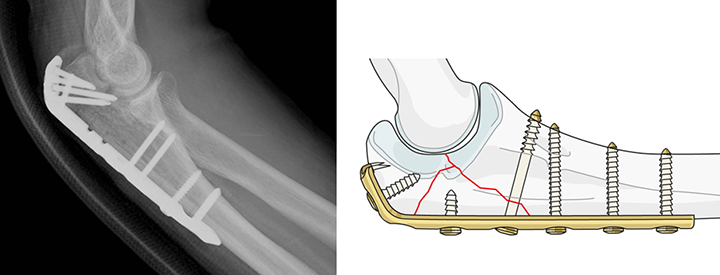

一般に、小さなかけらによる骨折が多いので、細い針金を巻き、鋼線や骨ネジなどを用いて固定する方法が良く行われています(図2)。また骨折した骨のかけらが、細かく裂けている場合や、怪我した方が高齢の場合、あるいは脆い骨による骨折の場合は、金属のプレートを用いる方法も行われています(図3)。

図3 金属プレート固定法(https://www.aofoundation.org)